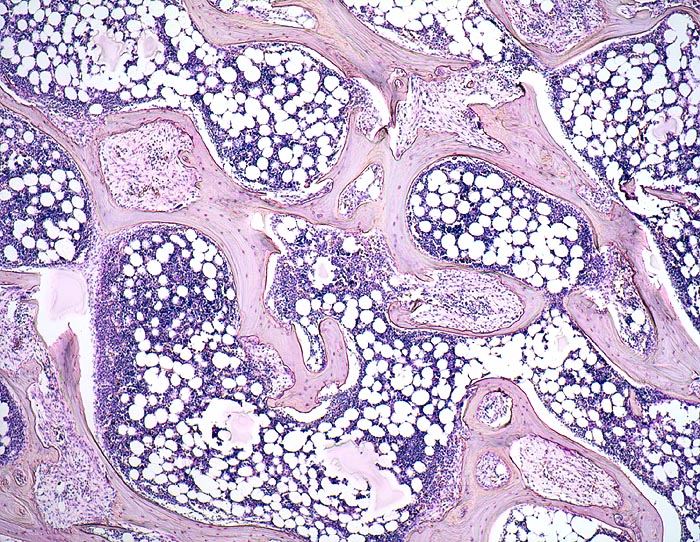

Fibroosteoklasie

Knochen, Becken

Spongiosabälkchen mit tiefen Resorptionslakunen, welche die Bälkchen z.T. tunnelartig aushöhlen. Regelrechtes blutbildendes Knochenmark.

Adenom der Nebenschilddrüse mit primärem Hyperparathyreoidismus. Nephrolithiasis.

Durch den massiven Knochenabbau kommt es zu einer Hyperkalzämie. Die damit verbundene Hyperkalzurie begünstigt eine Nephrolithiasis (10% der Patienten). Weitere Komplikationen sind rezidivierende Pankreatitiden, Neigung zu gastralen und duodenalen Ulzera, Gewichtsverlust, Obstipation und Knochenschmerzen.